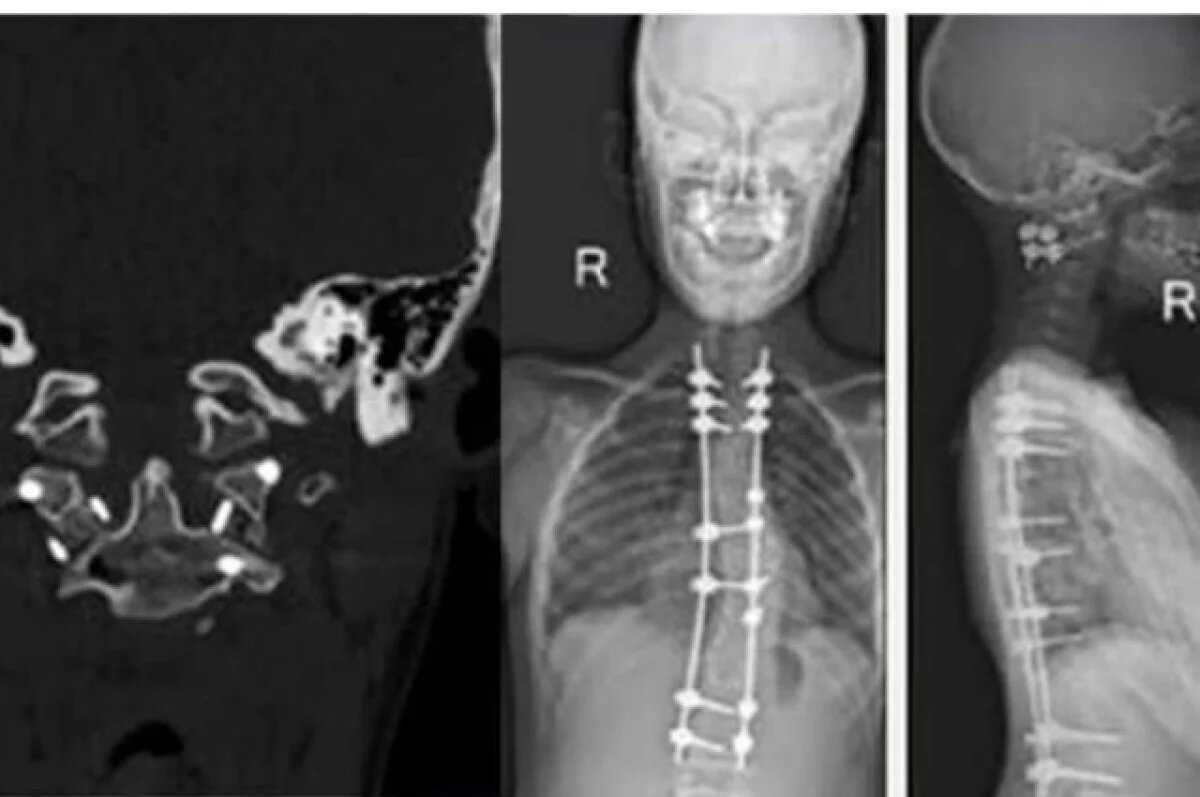

13-летний житель Перми, полностью парализованный после травмы, снова начал ходить благодаря хирургам Федерального центра травматологии и ортопедии имени Илизарова, сообщает пресс-служба Министерства здравоохранения Российской Федерации. Случай осложнялся редким генетическим заболеванием — синдромом Элерса — Данло, при котором соединительная ткань становится чрезмерно уязвимой. После несчастного случая подростка экстренно доставили в клинику центра. Врачи провели сложнейшую операцию на шейном отделе позвоночника: устранили сдавление спинного мозга и выполнили стабилизацию позвонков. После операции началась интенсивная реабилитация. Вскоре к мальчику вернулась чувствительность, и он сделал первые шаги с опорой. Для восстановления неврологических функций также применялась методика стимуляции спинного мозга. Сейчас состояние мальчика хорошее. Это уже не первый раз, когда в центре помогают этому пациенту — ранее врачи здесь же успешно исправили у него тяжелую деформацию позвоночника.

После несчастного случая подростка экстренно доставили в клинику центра. Врачи провели сложнейшую операцию на шейном отделе позвоночника: устранили сдавление спинного мозга и выполнили стабилизацию позвонков.

Это уже не первый раз, когда в центре помогают этому пациенту — ранее врачи здесь же успешно исправили у него тяжелую деформацию позвоночника.